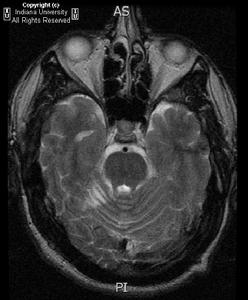

影像學表現:MR 腦溝腦回表現有界限清晰的小腦占位徵象,T2和 FLAIR 增強前後均顯示高信號,表現為“斑紋”狀(圖像如下)。彌散圖像在ADC上無減小。波譜分析NAA值上有增強的乳酸信號,另外有相對減少或正常的膽鹼信號。因此,可以利用磁共振波譜MRS來鑑別診斷膠質瘤。

CT 顯示有高密度“斑紋”,但增強後極少強化。